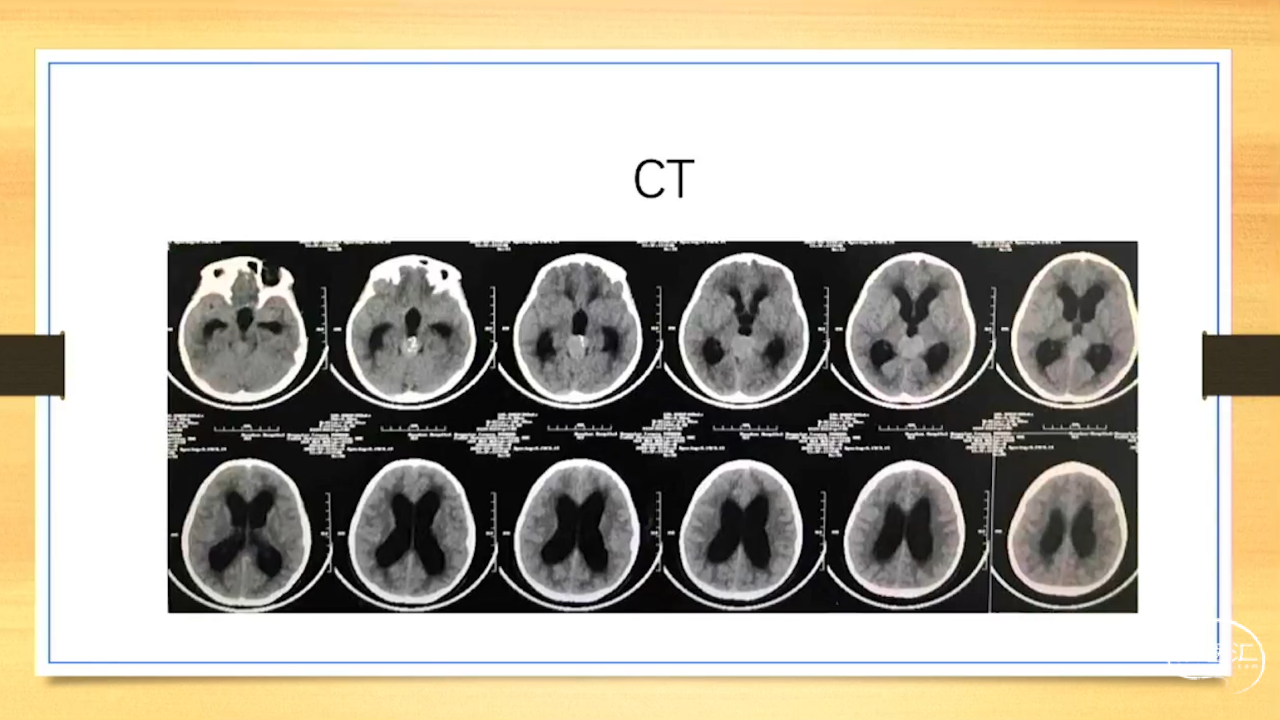

张荣教授:儿童颅内生殖细胞瘤的手术治疗

颅内生殖细胞肿瘤的治疗是手术、放疗、化疗、内分泌及其他多学科的整合治疗。及时、精准、合理的手术治疗是iGCT患者提高生存率、降低并发症、改善神经内分泌功能的关键。